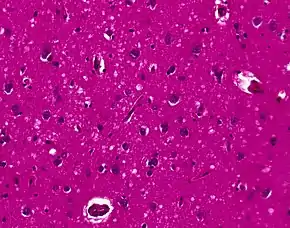

The symptoms of CJD are caused by the progressive death of the brain's nerve cells, which are associated with the build-up of abnormal prion proteins forming in the brain. When brain tissue from a person with CJD is examined under a microscope, many tiny holes can be seen where the nerve cells have died. Parts of the brain may resemble a sponge where the prions were infecting the areas of the brain.[17]

The classic histologic appearance is spongiform change in the gray matter: the presence of many round vacuoles from one to 50 micrometers in the neuropil, in all six cortical layers in the cerebral cortex or with diffuse involvement of the cerebellar molecular layer.[54] These vacuoles appear glassy or eosinophilic and may coalesce. Neuronal loss and gliosis are also seen.[55] Plaques of amyloid-like material can be seen in the neocortex in some cases of CJD.[56]

However, extra-neuronal vacuolization can also be seen in other disease states. Diffuse cortical vacuolization occurs in Alzheimer's disease, and superficial cortical vacuolization occurs in ischemia and frontotemporal dementia. These vacuoles appear clear and punched-out. Larger vacuoles encircling neurons, vessels, and glia are a possible processing artifact.[53]